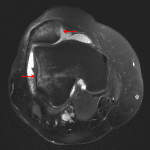

Indication: Knee pain

- No acute fracture

- Lateral patellar dislocation

- Moderate joint effusion

- Patellar dislocation

No acute fracture.

Lateral patellar dislocation.

Moderate joint effusion.

Joint spaces are maintained.

- The patella most commonly dislocates laterally, which is often transient, such that there may be no radiographic abnormalities by the time the patient is imaged

- MRI often shows a “kissing contusion” pattern with bone contusions along the medial patella and lateral femoral condyle at the sites of impact

- MRI may also show associated injury to the medial patellofemoral ligament (MPFL) or medial retinaculum